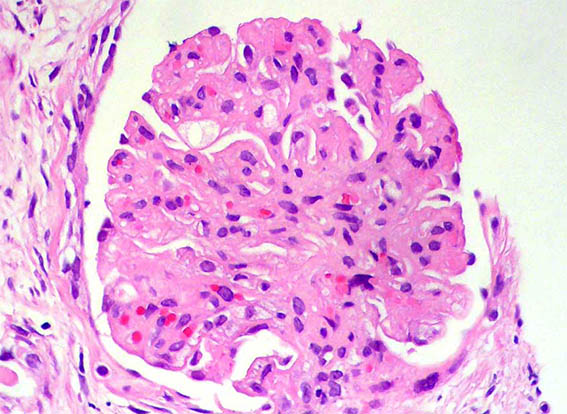

A 33-year-old man presented with pedal edema, persistent proteinuria and hypertension. Her past and family histories were unremarkable. Her blood pressure was 160/100 mm Hg. Physical examination revealed pedal and facial edema, without other alterations. Laboratory tests showed proteinuria of 4.7g/24 h, serum creatinine 1,0 mg/dL, microhematuria, normal serum complement levels, ANA negative; HIV, hepatitis B and C viral infections were negative. Ultrasound of the abdomen showed normal sized kidneys.

Kidney biopsy was performed. Look at the images.

Figure 1. H&E, X400.